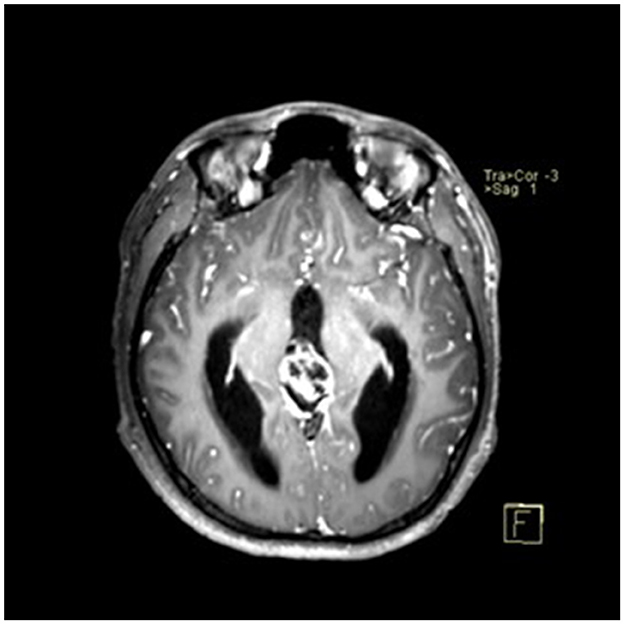

A 22-year-old male presented with intermittent dizziness and headache lasting for 2 weeks. MRI at admission revealed a cystic mass in the pineal region, accompanied by supratentorial hydrocephalus (Figures 3–5). No surgical contraindications were identified. After discussion with the patient's family, neuroendoscopic resection was performed via the Transfrontal-Transventricular-Transforaminal Approach. Intraoperatively, a 20 × 20 mm soft, well-vascularized tumor was found obstructing the cerebral aqueduct. The lesion had well-defined margins and was carefully dissected from surrounding adhesions, preserving adjacent veins and brain tissue. Macroscopic total resection was achieved en bloc (Figures 6–8). Postoperative day 1 MRI confirmed complete tumor removal and resolution of hydrocephalus (Figures 9–11). Postoperatively, no complications were observed. However, due to personal reasons, the patient was discharged on postoperative day 11. Histopathology confirmed a mixed germinoma. No recurrence or surgery-related complications were noted during follow-up.

Figure 3

Preoperative contrast-enhanced MRI (axial view) showing a cystic-solid mass in the pineal region with supratentorial hydrocephalus.